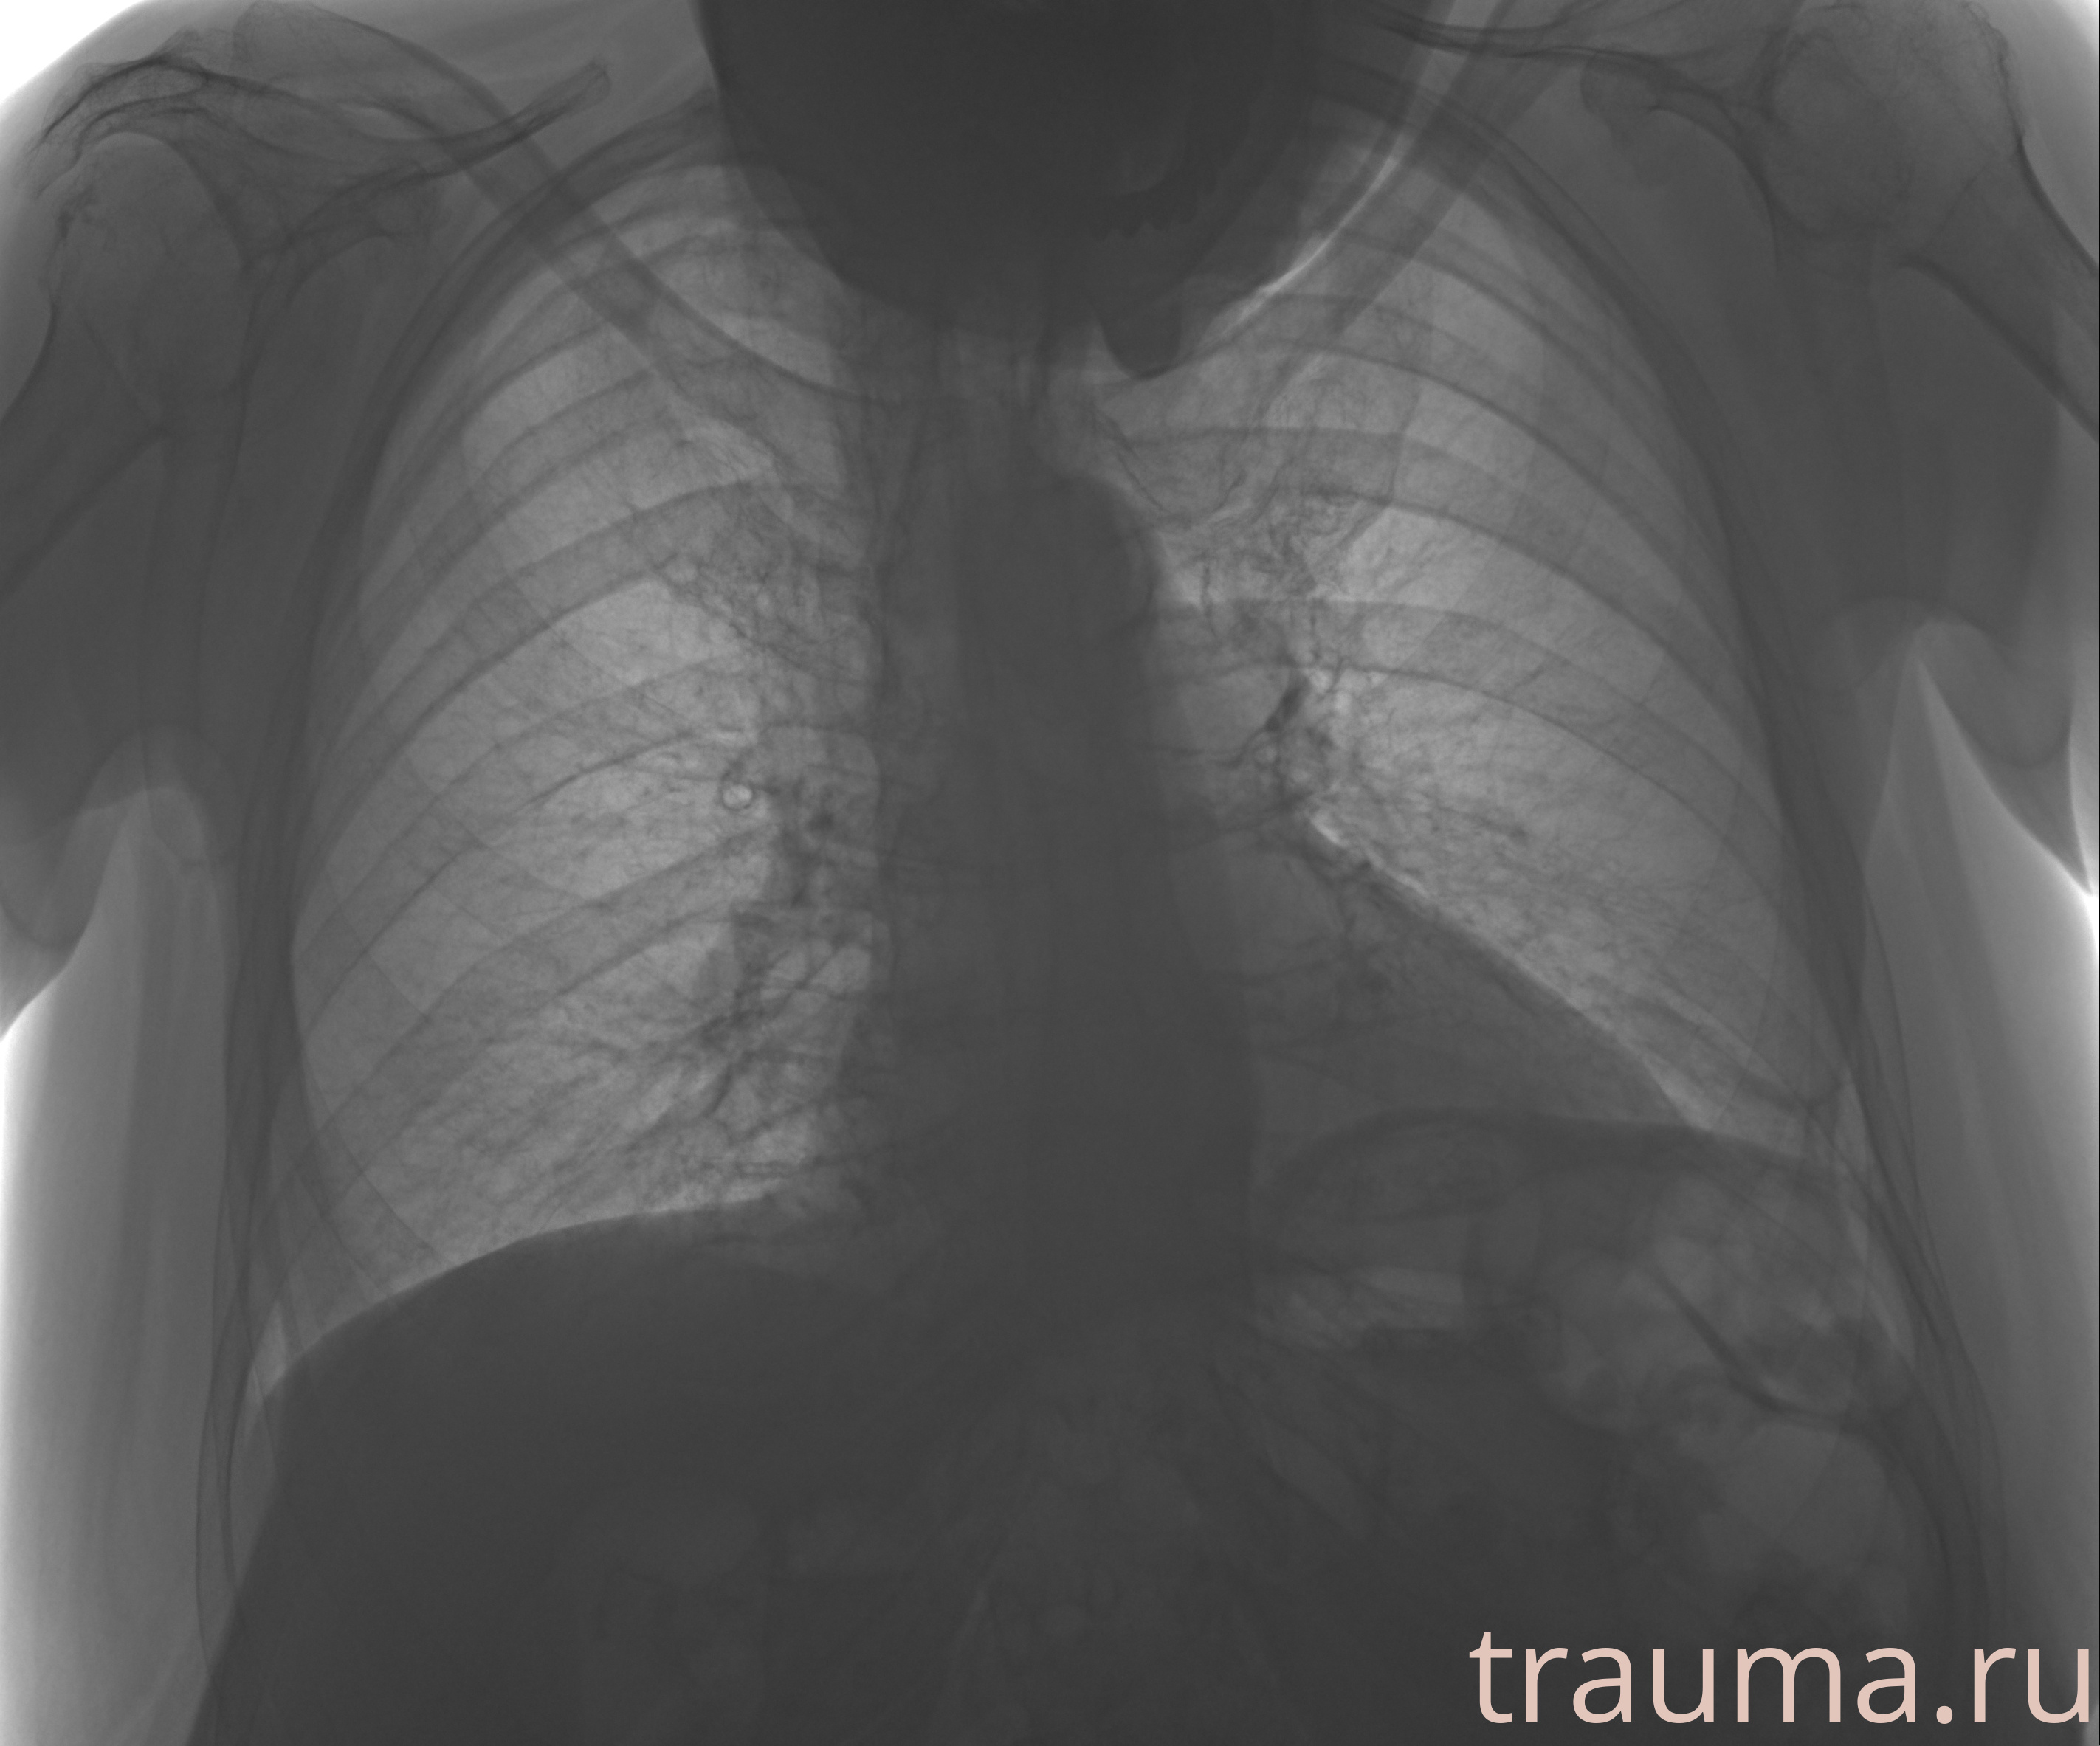

Рентгенограммы

Рентген на дому: по вашему адресу приезжает врач-рентгенолог, травматолог-ортопед с мобильным рентгеновским аппаратом, проводит диагностику травмы или заболевания, делает необходимые рентгенограммы, дает рекомендации по дальнейшему лечению. Получить качественные снимки в домашних условиях возможно благодаря уникальной методике, разработанной МосРентген Центром для института  Склифосовского